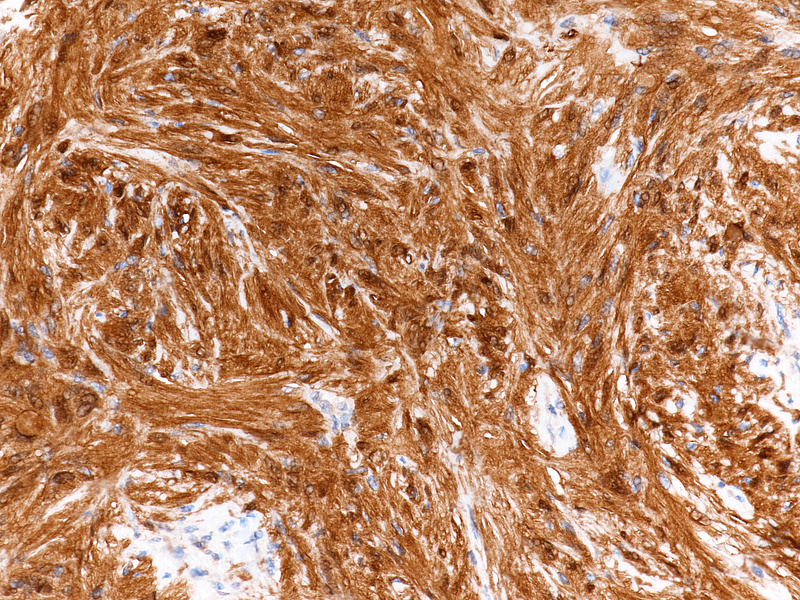

During laparoscopic surgery, the tumour proved to be confined to the appendix, with no other intra-abdominal findings (Panel A). The resection specimen disclosed a well circumscribed solid tumour, 4.2 cm in maximum diameter, with a homogeneously yellowish-white cut surface (Panels B and C).  Histologically, we observed a loose to densely cellular, spindled-cell neoplasia, arranged in fascicular and sweeping patterns (Panel D). Lymphoid aggregates, sometimes forming lymphoid follicles with germinal centres, were  found distributed at the periphery and also throughout the tumour (Panels E and F). The neoplastic cells had sparse cytoplasm and elongated, bland nuclei with inconspicuous nucleoli; focal and moderate atypia was noted (Panel G). Mitotic activity was <5mitoses/10HPF. Haemorrhage or necrosis were not observed. Upon immunohistochemistry, there was diffuse and strong positivity for S100 protein (Panel H) and moderate positivity for GFAP (Panel I). CD117 marked intralesional mast cells, whereas the tumour cells were negative (Panel J). Desmin and smooth muscle actin were negative (not shown).

Confirmation by immunostaining is required given the mimicry of many mesenchymal tumours and the rarity of appendiceal schwannomas. A characteristic finding is the strong and diffuse positivity for S100 protein. Variable staining for GFAP and CD34 is present. Markers for GIST (CD117, DOG-1) are negative and positivity in Cajal cell hyperplasia or in scattered intralesional mastocytes is an important pitfall to consider. Also, muscle markers (desmin, smooth muscle actin) must be negative.